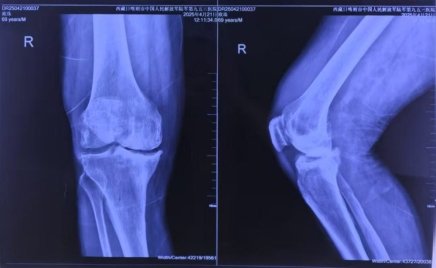

患者常年受双膝疼痛折磨,右膝严重内翻畸形伴骨缺损,步行百米即需歇息。传统手术面临三大“高原枷锁”:患者骨骼“塌方式”缺损,假体匹配难度倍增;医生需克服高原反应,设备需在低压低氧环境中稳定运行;生物膝严苛标准,截骨误差需小于1毫米,压力失衡将导致假体寿命骤降50%。

面对挑战,张瑗教授与九五三医院骨科扎西主任团队制定了创新性手术方案。依托元化智能锟铻全骨科手术机器人三维重建患者膝关节结构,智能匹配最佳生物膝假体型号及截骨角度;术中机器人辅助完成高精度截骨,为生物膝假体提供完美贴合面,结合压力垫片实时监测关节间隙压力,确保假体受力均衡;手术全程仅耗时2小时,出血量少,力线精准恢复至0°。术后第一天,患者已能下床并负重行走,步态轻盈,信心满满。